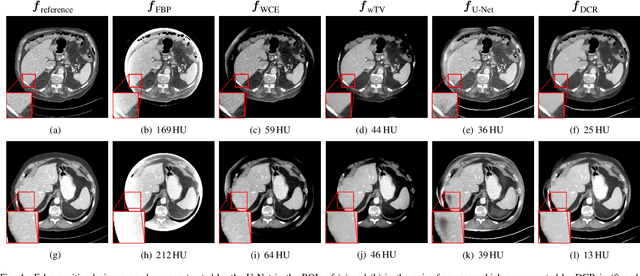

Image reconstruction from insufficient data is common in computed tomography (CT), e.g., image reconstruction from truncated data, limited-angle data and sparse-view data. Deep learning has achieved impressive results in this field. However, the robustness of deep learning methods is still a concern for clinical applications due to the following two challenges: a) With limited access to sufficient training data, a learned deep learning model may not generalize well to unseen data; b) Deep learning models are sensitive to noise. Therefore, the quality of images processed by neural networks only may be inadequate. In this work, we investigate the robustness of deep learning in CT image reconstruction by showing false negative and false positive lesion cases. Since learning-based images with incorrect structures are likely not consistent with measured projection data, we propose a data consistent reconstruction (DCR) method to improve their image quality, which combines the advantages of compressed sensing and deep learning: First, a prior image is generated by deep learning. Afterwards, unmeasured projection data are inpainted by forward projection of the prior image. Finally, iterative reconstruction with reweighted total variation regularization is applied, integrating data consistency for measured data and learned prior information for missing data. The efficacy of the proposed method is demonstrated in cone-beam CT with truncated data, limited-angle data and sparse-view data, respectively. For example, for truncated data, DCR achieves a mean root-mean-square error of 24 HU and a mean structure similarity index of 0.999 inside the field-of-view for different patients in the noisy case, while the state-of-the-art U-Net method achieves 55 HU and 0.995 respectively for these two metrics.